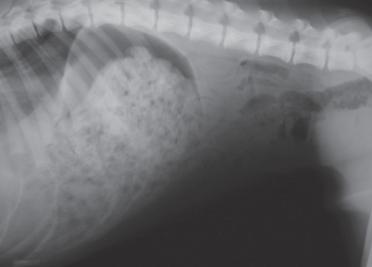

后续体格检查,体温38°C,呼吸55次/min,仔细观察腿部并未发现异常,但呼吸明显急促,需进一步影像学检查才知道结果。X光片结果显示肺部显影明显异常,结合上述情况后,确诊为创伤性膈疝,应立即开始膈疝修复手术。

右侧腹部X光片